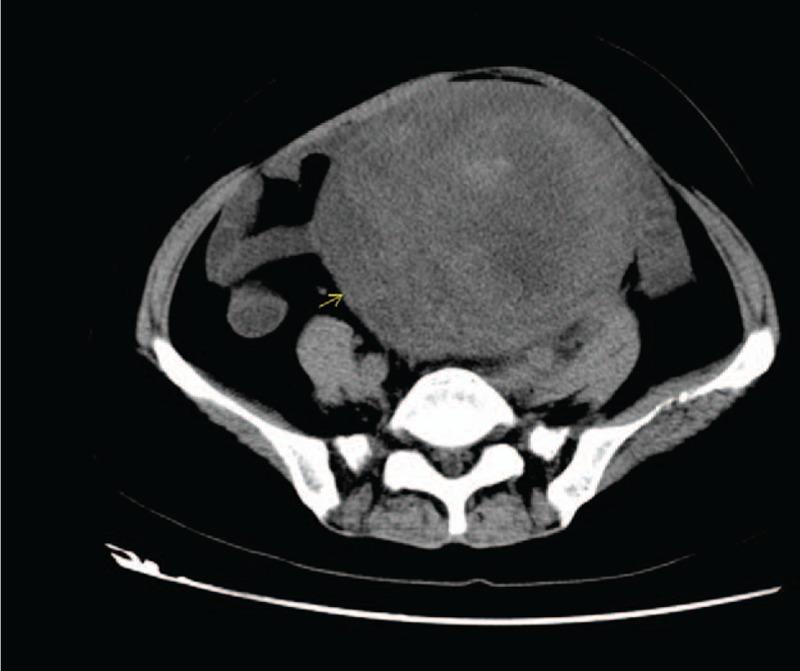

A mass was revealed at the left uterine appendage by pelvic ultrasound and CT.Pathology and immunohistochemistry confirmed the diagnosis of the left ovarian atypical leiomyoma.

盆腔超声和CT检查显示左侧子宫附件有一肿块。病理及免疫组化确诊为左侧卵巢非典型平滑肌瘤。